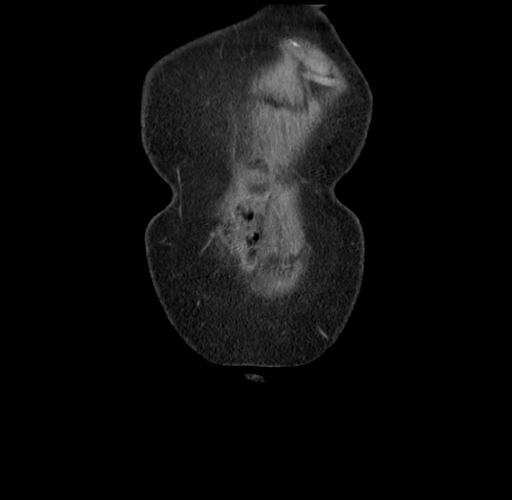

MRI T1

Imaging analysis

Based on your CT findings, which issue(s) would give reason for "planned slowing down moment(s)" in this case?

Considering a standard right hepatectomy procedure, what step(s) of the operation would you do differently in this case?